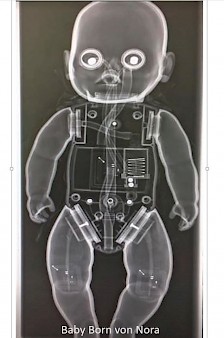

Erst das Kuscheltier - dann das Kind

Galerie der Kuscheltiere

Kinder kommen oft sehr ängstlich mit Kuscheltieren oder Puppen zum Röntgen. Um den Kindern diese Angst zu nehmen, kann man vor deren neugierigen Augen, zuerst die kuscheligen Begleiter unter die Röhre legen.

Spätestens wenn die Kinder die Bilder Ihrer Kuscheltiere sehen ist die Angst vorm Röntgen meist vergessen. So wie bei den unten abgebildeten Bildern.

Galerie wird ständig erweitert!